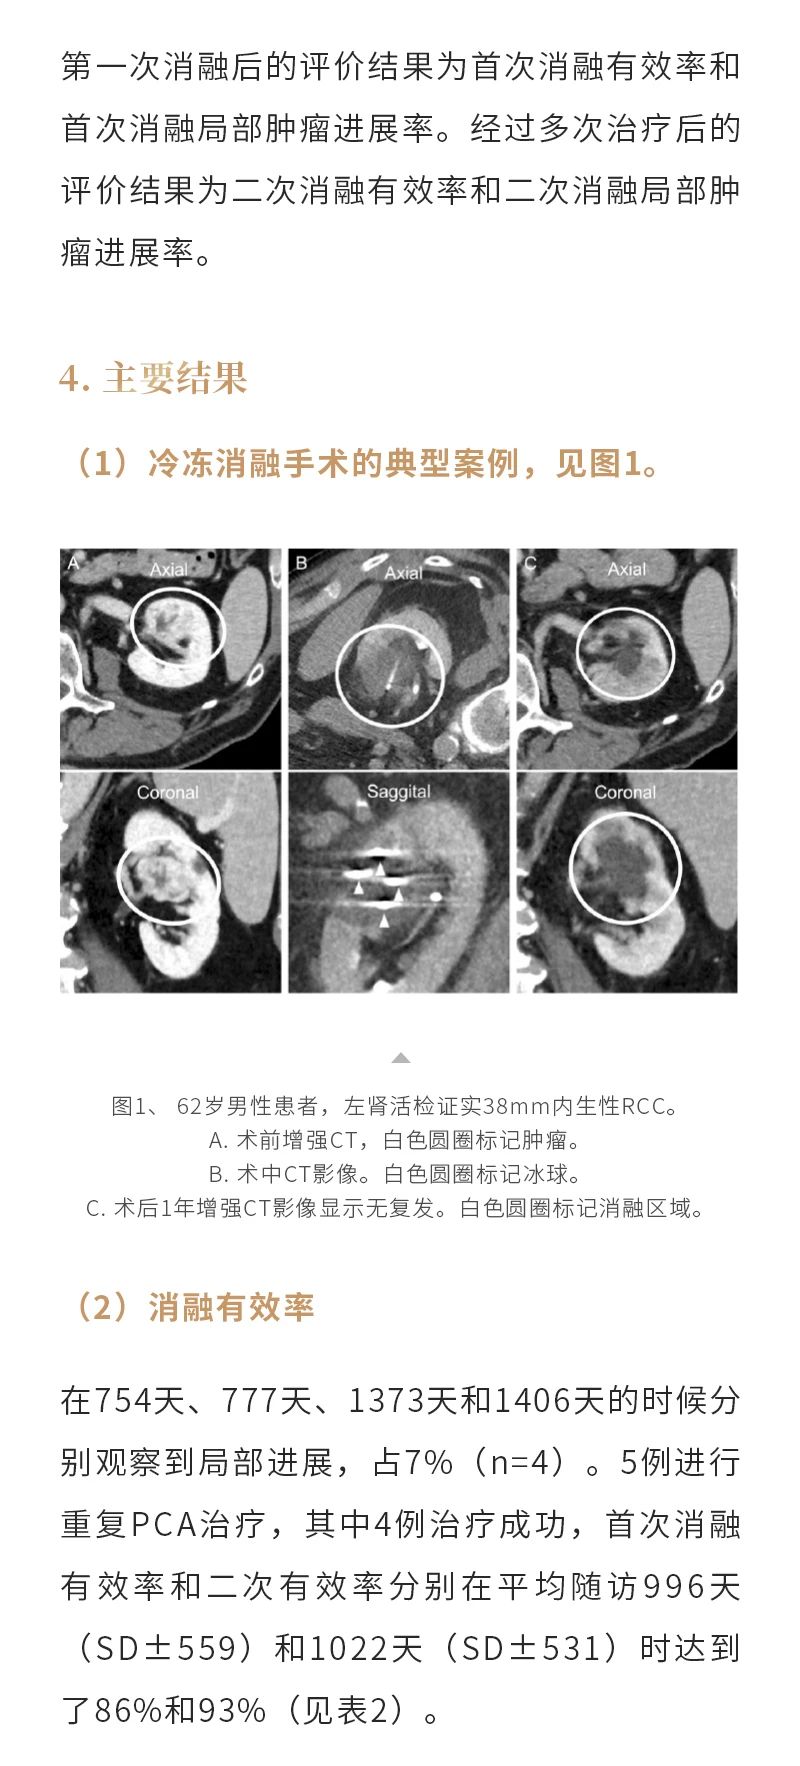

冷凍消融腎癌——【海杰亞科研資訊】第284期